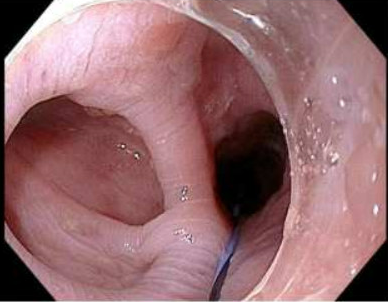

Zenker peroral endoscopic myotomy was performed under general anesthesia. EGD was performed and all the food contents from the pouch were removed (Fig. 2). A guidewire was passed through the esophageal lumen for identification during procedure. Saline with methylene blue was injected along the cricopharyngeal ridge and a mucosal incision was made along the ridge using a Triangular tip knife (TTJ Olympus, America) using ENDOCUTQ current (ERBE). Submucosal dissection was done to form a tunnel using spray coagulation and the esophageal mucosa and diverticular mucosa were separated from the cricopharyngeus muscle. Then a complete cricopharyngeal myotomy was performed using the same Triangular tip knife until the buccopharyngeal fascia was reached (Fig. 4 & 5). After complete hemostasis, the mucosal incision was closed using through-the-scope clips (Microtek). A total of five clips were used for the closure (Fig. 6).

Figure 2: Procedural esophagogastroduodenoscopy showing a Zenker diverticulum with food and luminal contents.

Figure 2